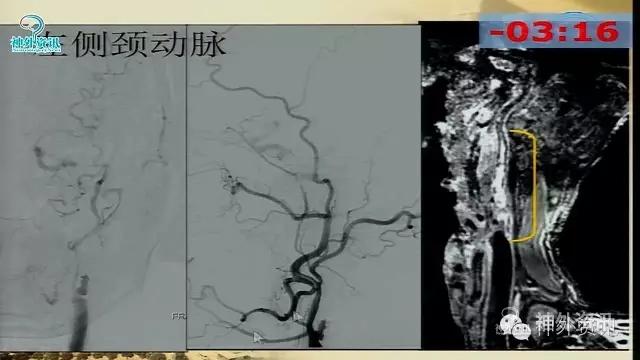

万杰清教授:慢性颈动脉闭塞再通技术及临床效果